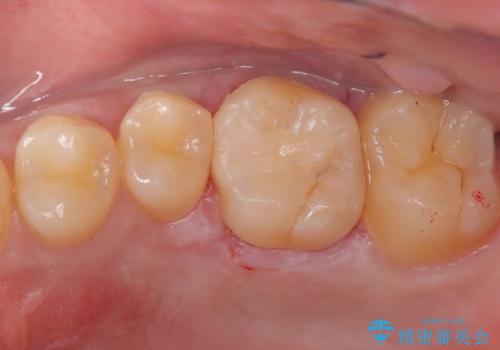

虫歯の再発リスクを減らすセラミックインレー

- 他院でインビザラインの治療中に虫歯を発見されたため、治療を希望され来院された患者様です。

セラミックインレーにて治療を行いました。

セラミックインレーは適合が良く、虫歯の再発リスクを減らすことができます。